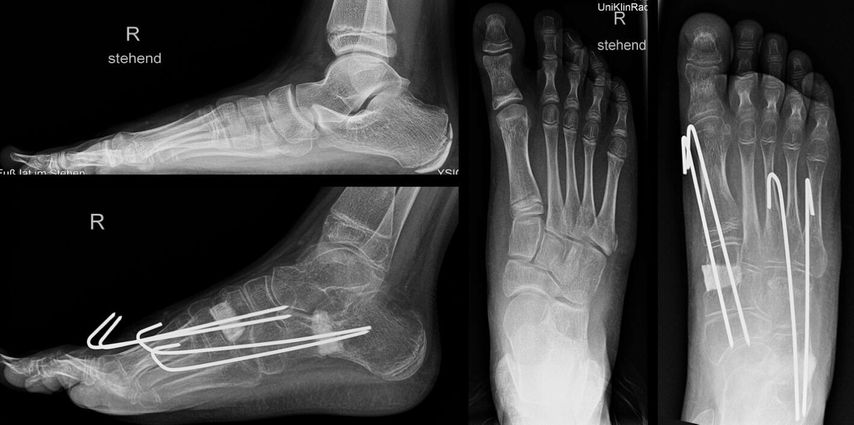

Bei einem 9-jährigen Mädchen mit angeborenem Knick-Senk-Fuß beidseits wurde ein kommerziell verfügbarer Allograft-Knochenblock zur Evans-Osteotomie erfolgreich angewendet. Im Rahmen einer ersten Operation wurde der rechte Fuß adressiert (Abb. 1) und im Verlauf ein Jahr später das gleiche Verfahren auf der Gegenseite problemlos eingesetzt. In der Verlaufskontrolle 1 Jahr postoperativ zeigen sich eine gute knöcherne Einheilung, eine adäquate Fußaufrichtung und eine Verlängerung der lateralen Säule. Das Allograft ist nativradiologisch noch abgrenzbar. Ein weiterer Fall einer komplikationslosen Evans-Osteotomie mit kommerziellem Allograft-Knochenblock ist der eines 14-jährigen Jungen mit Knick-Senk-Fuß links. Abgebildet ist die Verlaufskontrolle 6 Wochen postoperativ, wobei im Rahmen der ambulanten Kontrolle die Kirschnerdrähte nach 6 Wochen entfernt wurden. Ein Folgeröntgen ist noch ausständig (Abb. 2). Bei einer 15-jährigen Patientin mit schmerzhaftem Knick-Senk-Fuß beidseits zeigt sich ebenso eine adäquate Fußkorrektur in der Jahreskontrolle nach Evans-Osteotomie mit Allograft-Knochenblock rechts. Eine Versorgung der Gegenseite ist geplant (Abb. 3). Auch im Fall eines 11-Jährigen mit Serpentinenfüßen kamen bereits Allograft-Knochenblöcke erfolgreich zum Einsatz: Präoperativ zeigte sich hier ein Rückfußvalgus mit Vorfuß adductus und damit verkürzter lateraler Fußsäule. Als operative Sanierung wurde eine Fußkorrektur durchgeführt, die Aspekte einer modifizierten Cotton-, Evans- und Cuboid-Osteotomie enthält. In der postoperativen Röntgenaufnahme 8 Wochen später zeigte sich eine gute knöcherne Einheilung bei stabiler Korrektur, sodass die Drähte gezogen werden konnten (Abb. 4).

Abb. 4: 11-jähriger Junge mit Serpentinenfüßen, prä- und postoperative Röntgenaufnahmen, 8 Wochen nach komplexer Fußkorrektur mit Allograft-Knochenblöcken im Os cuneiforme mediale und Kalkaneus mit Drahtstabilisierung in situ